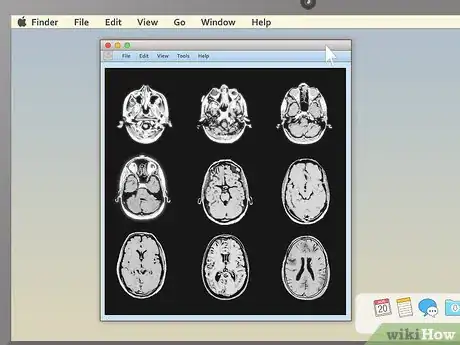

3Pick an appealing series layout. MRI programs almost always have the ability to display more than one image at once. This makes it convenient for doctors to compare different views of the same area or even MRIs taken at different times. For most non-doctors, it's easiest to simply choose a one-image-at-a-time layout and cycle through the images individually. However, there should be onscreen instructions to show two, four, or many more images at once, so feel free to play around with this feature.